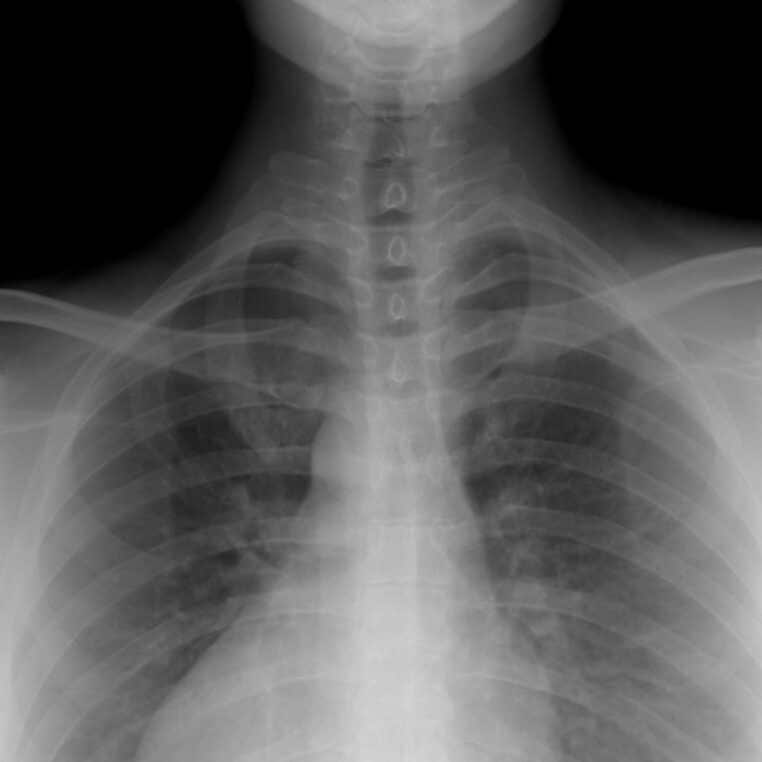

Une côte supplémentaire

Le corps humain est normalement composé de 24 côtes, mais certaines personnes en ont 25. C’est un phénomène rare qui touche moins de 1% des personnes. Cette caractéristique s’appelle le syndrome de la côté cervicale.

Ce syndrome se caractérise par l’existence d’une côte cervicale supplémentaire.